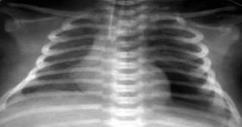

Выраженное снижение пневматизации легких, воздушные бронхограммы, границы сердца практически не различимы, стёрты (Рис.6).

Рисунок 6. РДС. Рентгенограмма грудной клетки в прямой проекции, в горизонтальном положении. Интенсивное мелкоточечное затемнение легочных полей - с-м "матового стекла", на фоне которого не дифференцируется тень средостения. Визуализируются линейные просветления, обусловленные заполненными воздухом бронхами - "воздушная бронхограмма". ( Диагностика и лечение РДС недоношенных // метод. рекомендация, 2007)